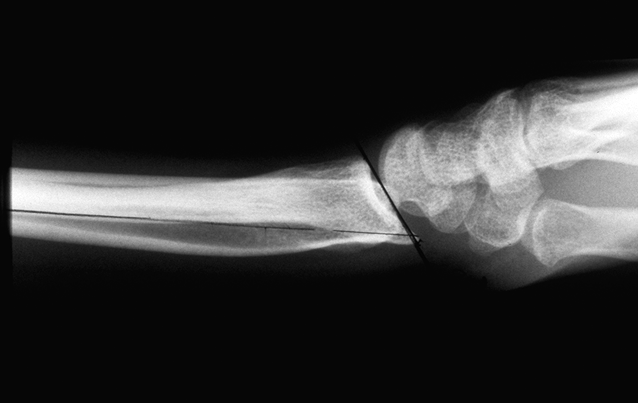

Case 4 Preop